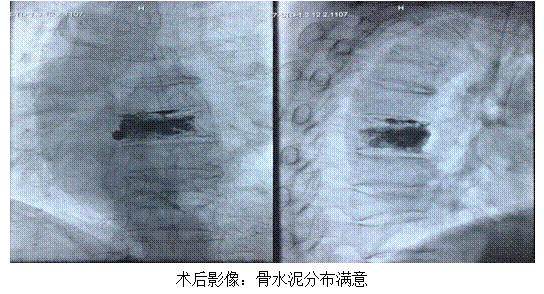

黃奶奶是一位肝癌術(shù)后復(fù)發(fā)患者,近1個(gè)多月來(lái)出現(xiàn)背部的疼痛不適,日漸加重,活動(dòng)時(shí)疼痛癥狀加劇,后發(fā)展至無(wú)法起床,生活不能自理。黃奶奶在門(mén)診口服止疼藥物后,癥狀改善不明顯,聽(tīng)他人介紹來(lái)到腫瘤介入科門(mén)診就診。經(jīng)全脊柱磁共振檢查,發(fā)現(xiàn)黃奶奶胸6椎體明顯水腫并伴有骨質(zhì)破壞,結(jié)合病史考慮系肝癌胸6椎體轉(zhuǎn)移。經(jīng)過(guò)科室團(tuán)隊(duì)的病情討論,考慮為其進(jìn)行DSA下經(jīng)皮胸6椎體成形術(shù)。經(jīng)過(guò)與患者家屬的充分溝通和術(shù)前精心的準(zhǔn)備,5月28日,科室團(tuán)隊(duì)為其順利實(shí)施手術(shù),手術(shù)時(shí)間僅20分鐘,手術(shù)結(jié)束后黃奶奶背部疼痛立刻得到了緩解。黃奶奶返回病房臥床兩小時(shí)后,即可下床自由活動(dòng),手術(shù)第二日黃奶奶出院。

目前經(jīng)皮椎體成形術(shù)廣泛應(yīng)用于椎體壓縮性骨折、骨轉(zhuǎn)移性腫瘤患者,在患者病變椎體內(nèi)注射PMMA后,可以恢復(fù)脊柱形態(tài),同時(shí)其放熱效應(yīng)可殺死腫瘤組織并破壞周圍神經(jīng),達(dá)到穩(wěn)定椎體形態(tài)及緩解疼痛的作用。椎體轉(zhuǎn)移性骨腫瘤患者和椎體骨折行PVP可立即緩解疼痛,同時(shí)增加了椎體強(qiáng)度,具有防止病理性骨折、改善腫瘤患者生活質(zhì)量和延長(zhǎng)患者生存時(shí)間的作用。